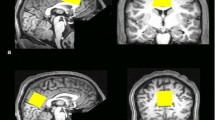

MP-RAGE images from one subject from the hippocampus data set (left) and one subject from the PCC data set (right). The nominal positions of the selected voxel are indicated by the red box. The (2 \(\times\)2 \(\times\)5) cm3 voxel is placed at the center of the hippocampus and aligned such that the long axis of the hippocampus is parallel to the voxel. A non-oblique (3\(\times\)3\(\times\)3) cm3 voxel is placed in the PCC. The insert shows the voxel positions of the GABA 3.0 ppm and the GABA 1.9 ppm resonance. The effective editing volume is the overlap of both

10 young healthy volunteers (\(26.6 \pm 4.7\) years, 5 females) participated in this study. Written informed consent was given by all subjects before examination. A whole-brain, high-resolution, T1-weighted MP-RAGE [15] image was acquired for each subject. This image was used to guide the placement of a (2 \(\times\) 2 \(\times\)5) cm3 voxel centered around the hippocampus, as shown in Fig. 2. Afterwards, the \(B_1\) amplitude was manually adjusted based on \(B_1\) mapping, utilizing 3DREAM [16]. The sLASER localization is quite insensitive against \(B_1\) variation. However, this is not the case for the MEGA pulses, rendering careful \(B_1\) adjustments necessary. Three circular regions of interest, concentric to the spectroscopic voxel in different orientations, were defined roughly of the size of the voxel. Based on the \(B_1\) map, the voltage needed for perfect refocusing within these regions was calculated and manually set. Subsequently, an automated 2-step \(B_0\) shimming procedure was applied. A GRE-based \(B_0\) map was acquired and shim values were calculated based on the selected spectroscopic voxel. Using the calculated shim currents, this procedure was repeated in a second step.